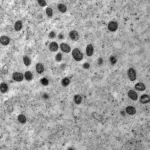

Varíola dos macacos

Monkeypox no Amazonas

Mais 13 casos de varíola dos macacos são registrados no Amazonas

A FVS repassou algumas orientações para se prevenir contra a doença